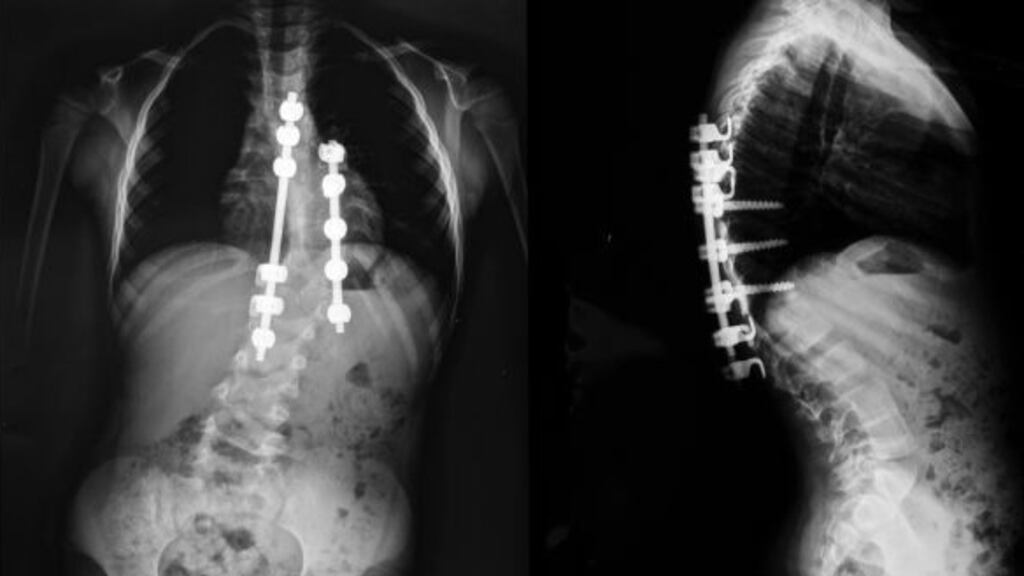

In the three months between diagnosis and surgery, the curvature of her spine went from 42 degrees to 62 degrees.

She was in first year in secondary school in 2000 when the rods were put in, in the children's hospital in Crumlin, to help straighten her back.

In 2014 the rods got infected. Because she was an adult, it was Tallaght Hospital that dealt with her then. No antibiotics were working and the infection would enter her bloodstream if it was not dealt with, so the rods had to come out.

But she knew she needed rods again, “otherwise I’d be kind of like bent over and I’d have different health issues in about 10 years”.

There followed years of appointments. “Your heart and lungs and organs could be affected by it. I was having numerous scans and X-rays.”

Along with the beds and resources, there are the complexities of her case. “I had three different curves in my spine – at the top, middle and bottom, which was the most painful.”

The case “wouldn’t be as complex if you hadn’t had spinal surgery. My spine is fused in different areas.”